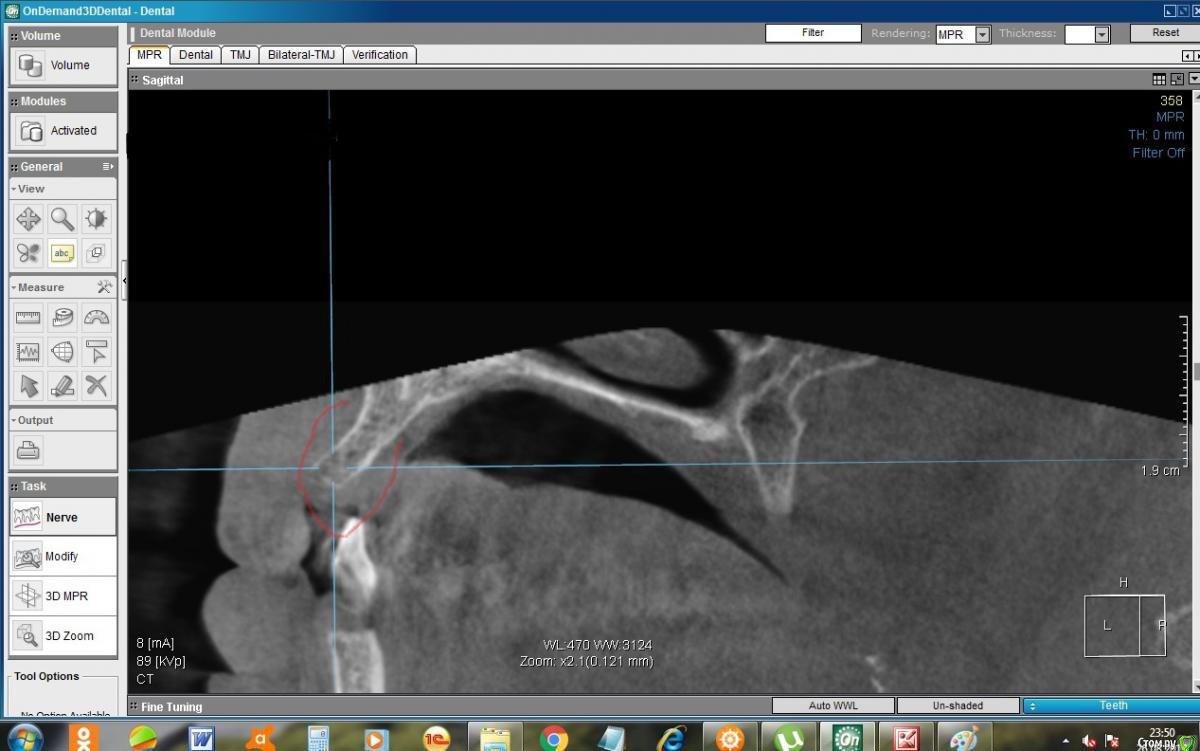

konst2009 Опубликовано 26 августа, 2019 Поделиться Опубликовано 26 августа, 2019 Здравствуйте.Два с половиной месяца назад удалил верхние передние 4 зуба. Вчера сделал KT. В сагиттальной проекции на месте лунок удаленных зубов вместо ожидаемой костной ткани как будто пустота, где-то даже губная пластина не просматривается. Срезы между лунками: Такое разве пригодно для имплантации? Что делать, ждать? Ссылка на комментарий

konst2009 Опубликовано 27 августа, 2019 Автор Поделиться Опубликовано 27 августа, 2019 Здравствуйте! После удаления зуба,объём костной ткани неминуемо уменьшается,чем больше времени после удаления-тем меньше костной ткани останется Понятно, но в лунках, если я правильно понимаю, после удаления сначала образовывается кровяной сгусток, а потом костная ткань, а ее почему-то на КТ не видно, как будто там пустота, как это можно объяснить? Ссылка на комментарий

колесников Опубликовано 27 августа, 2019 Поделиться Опубликовано 27 августа, 2019 Слабоминерализованая,потому не контрастируется Ссылка на комментарий